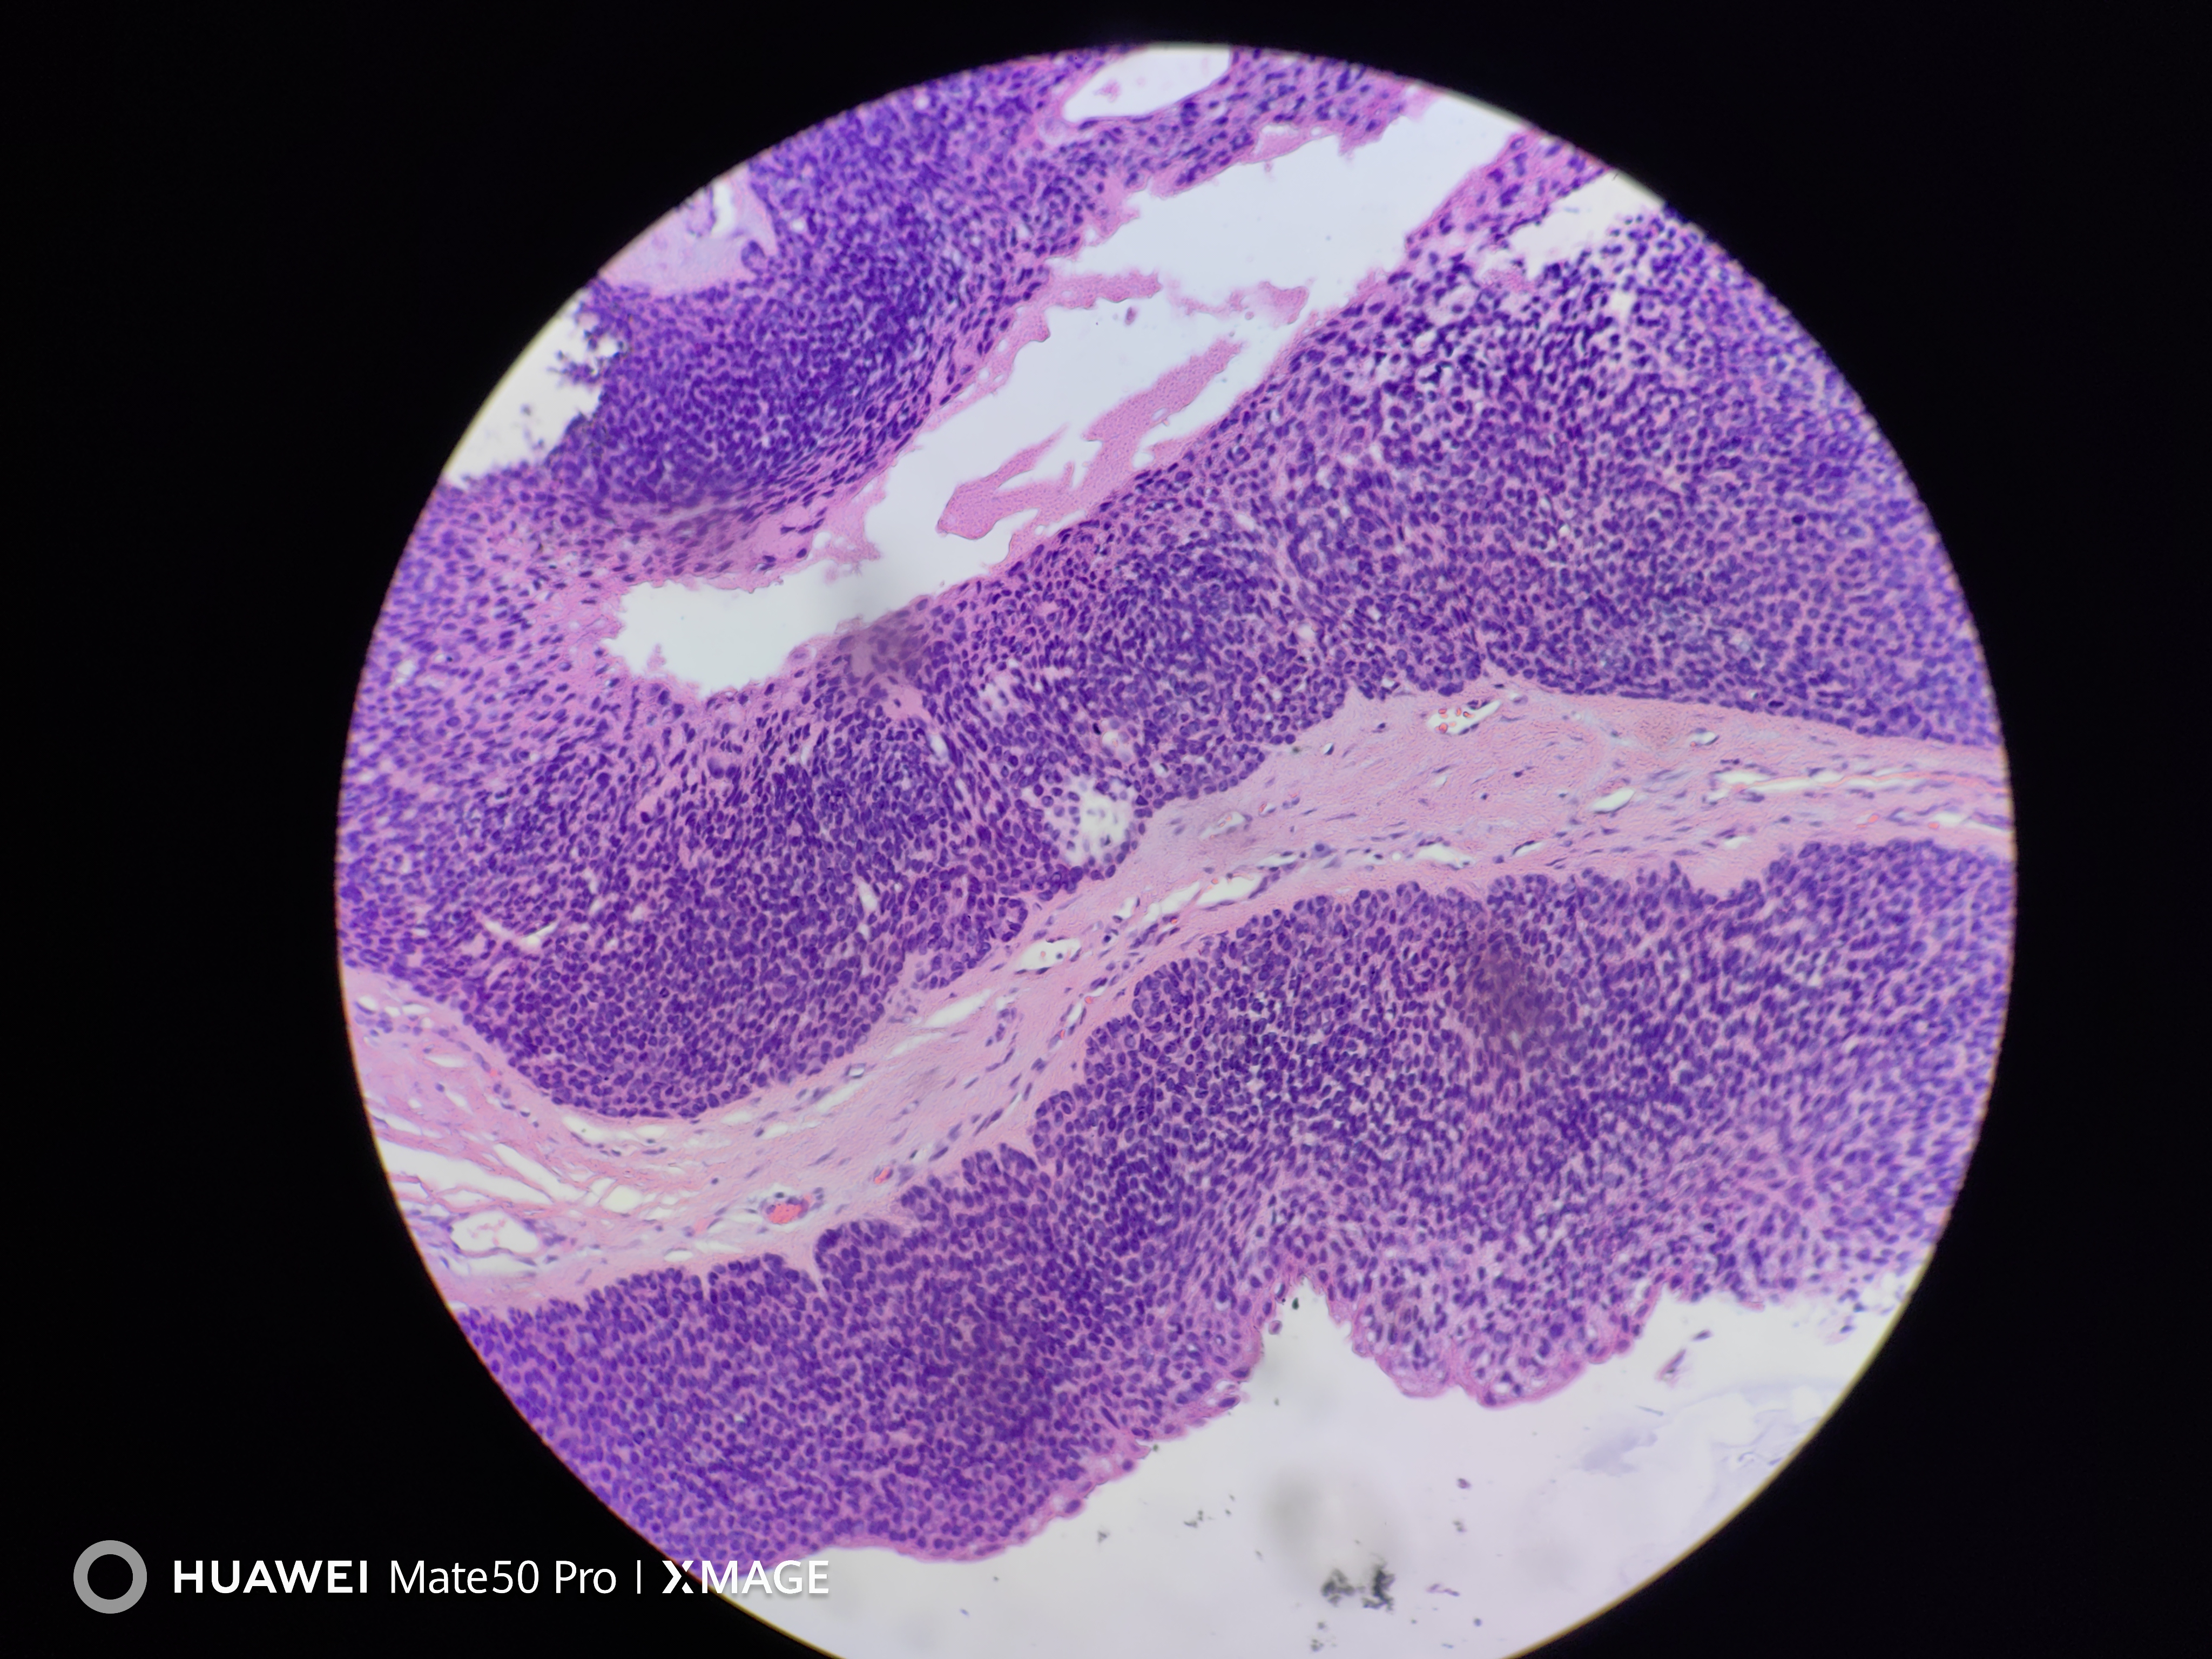

头皮肿物

头皮皮肤肿物3年余

头皮皮肤肿物

灰褐不整形组织一块,大小2.0*1.7*1.0cm,表面覆梭皮,切面灰白灰褐,实性质中。

考虑:汗孔瘤or圆柱瘤?

汗孔样汗腺瘤。

皮脂腺瘤

皮脂腺分化及导管

汗孔瘤伴皮脂腺分化。